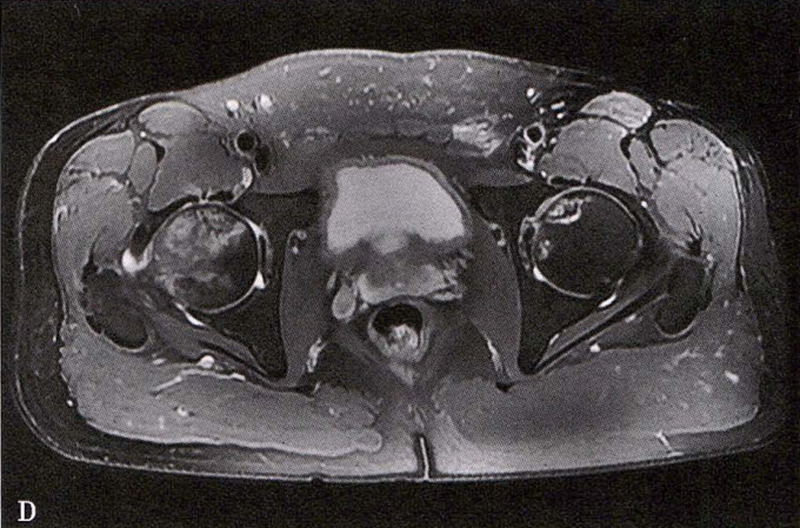

MRI示双侧股骨头坏死,冠状面显示右侧股骨头坏死(图A、C),横断面显示双侧股骨头坏死(图B、D);T1加权像(图A、B)显示硬化带为低信号,T2加权像(图C、D)显示右侧骨坏死硬化带外围高信号的骨髓水肿,左侧无骨髓水肿。

A.男性,71岁,双侧股骨头坏死,右侧Ⅰ期、左侧Ⅲ期。X线片示双侧股骨头形态可,右股骨头未见明显密度改变,左股骨头关节面下见局限性骨密度减低及增高区(A1)。MRI(T2加权像)示右股骨头内双线征,左侧不规则形混杂信号,坏死区远端骨髓水肿(A2、A3)。

B.男性,31岁,双侧股骨头坏死,双侧均为Ⅲ期。X线片示双侧股骨头密度不均、股骨头稍变扁(B1)。MRI(T1加权像)示股骨头内多发不规则信号带(B2),股骨头内凸向大转子的双线征(白色箭)和软骨下骨骨折(白色三角)。